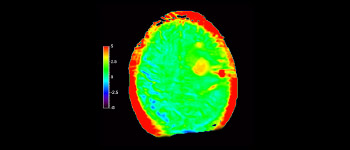

Brain lesion

with 3D APT